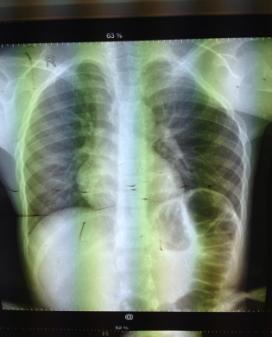

Пациент

Т.Е., 9 лет, рентген в прямой и боковой проекциях